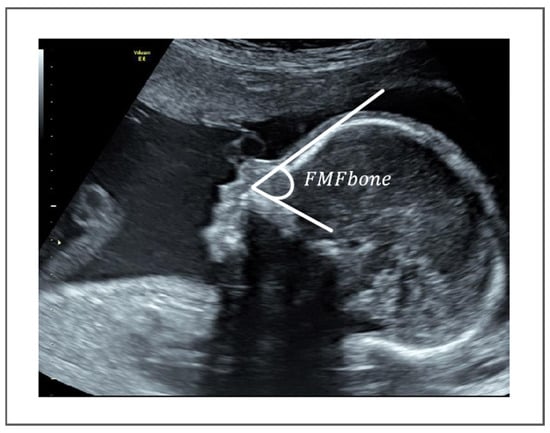

Automatic Measurement of Frontomaxillary Facial Angle in Fetal Ultrasound Images Using Deep Learning